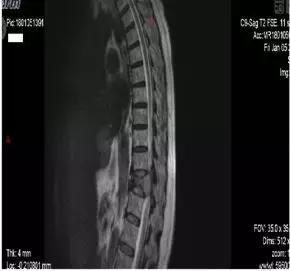

胸腰椎MRI显示多处骨质异常信号

根据检查结果,接诊医生高度怀疑李阿姨是多发性骨髓瘤,遂转入血液内科。

因多发性骨髓瘤会破坏骨骼,影像学会表现为虫蚀样改变、骨质疏松、骨折等,因此当出现不明原因的骨痛、骨折,同时伴有贫血、肾功能不全时,应高度警惕,尽快至血液科进行筛查。